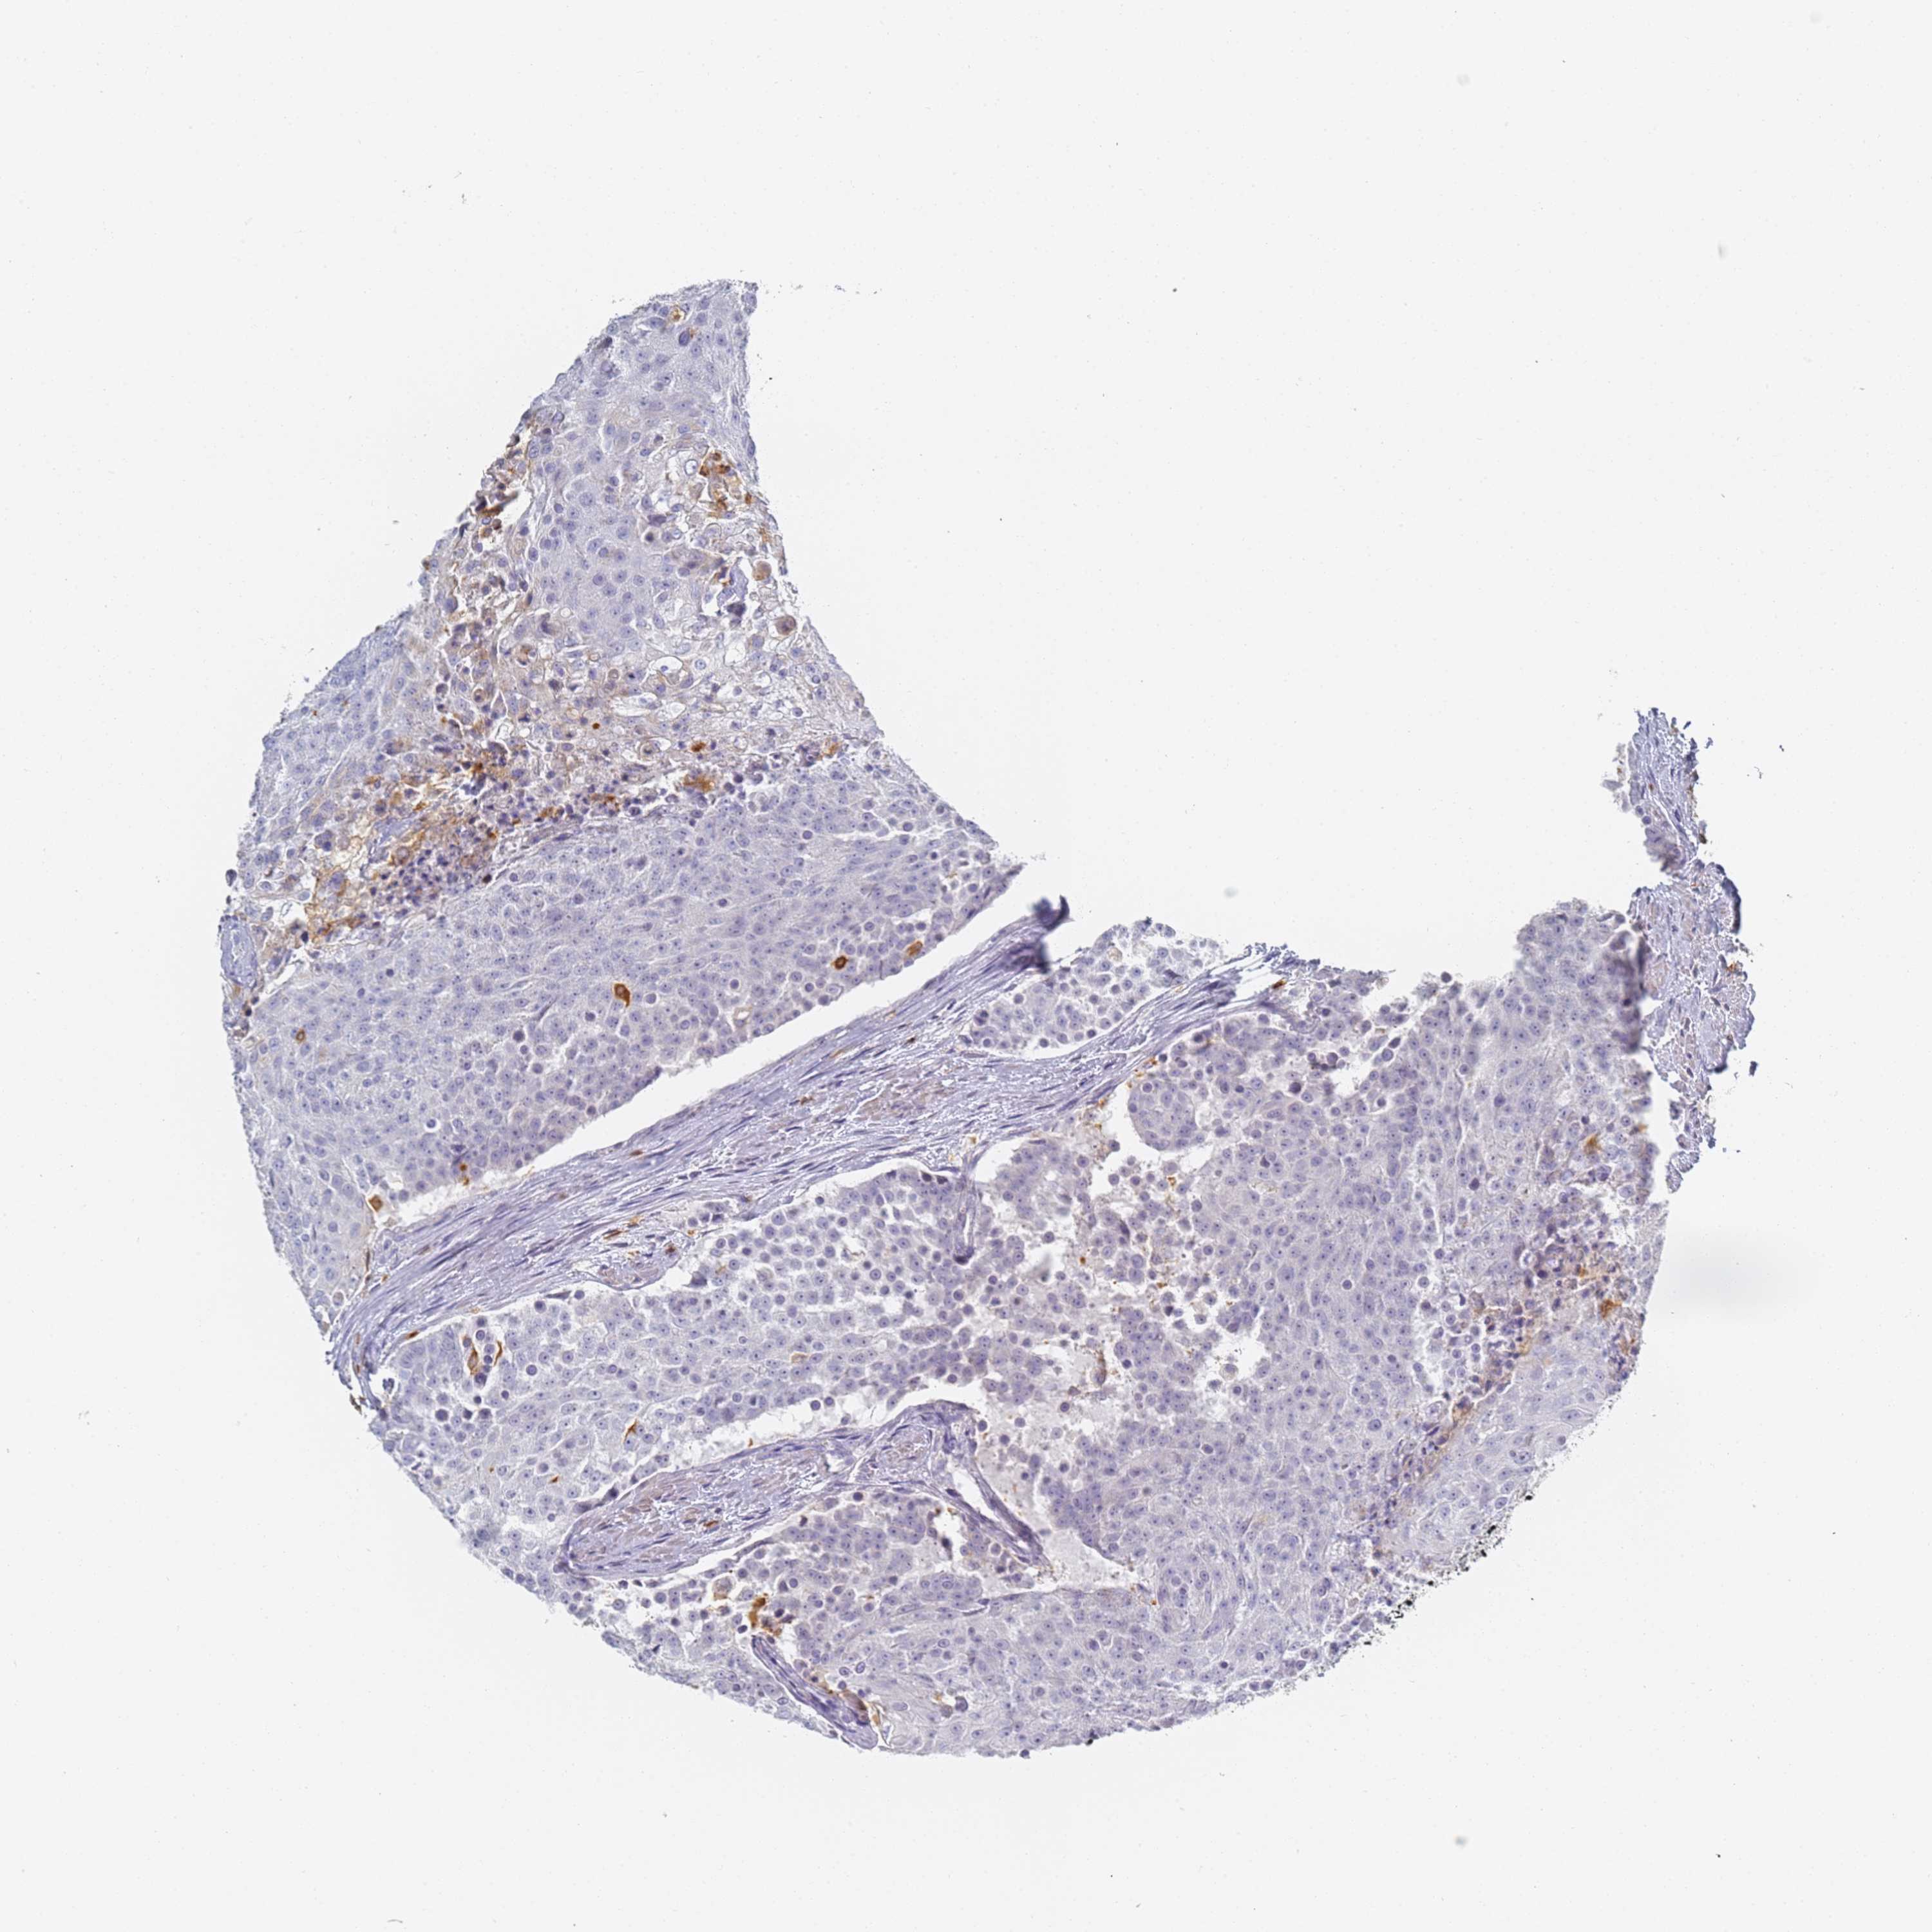

UROTHELIAL CANCER - Protein expressioni

A mouse-over function shows sample information and annotation data. Click on an image to view it in a full screen mode. Samples can be filtered based on level of antibody staining by selecting one or several of the following categories: high, medium, low and not detected. The assay and annotation is described here.

Note that samples used for immunohistochemistry by the Human Protein Atlas do not correspond to samples in the TCGA dataset.

Antibody stainingi

Antibody staining in the annotated cell types in the current human tissue is reported as not detected, low, medium, or high, based on conventional immunohistochemistry profiling in selected tissues. This score is based on the combination of the staining intensity and fraction of stained cells.

Each image is clickable and will lead to virtual microscopy that enables deeper exploration of all samples and also displays staining intensity scores, fraction scores and subcellular localization as well as patient and tissue information for each sample.

Antibody HPA038666

Antibody HPA038667

Urothelial carcinoma, High grade

Urothelial carcinoma, Low grade